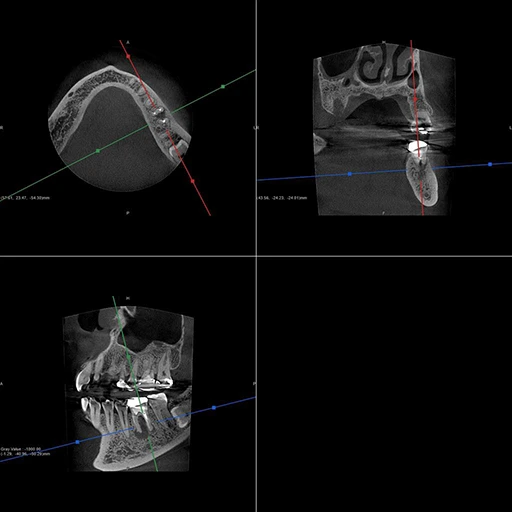

40代、女性、左下噛むと痛いこと主訴に来院され、インプラント治療を行いました。

| 診断結果 | 左下6番歯根破折 |

| 治療内容 | 抜歯即時インプラント |

| 治療期間 | 8週間 |